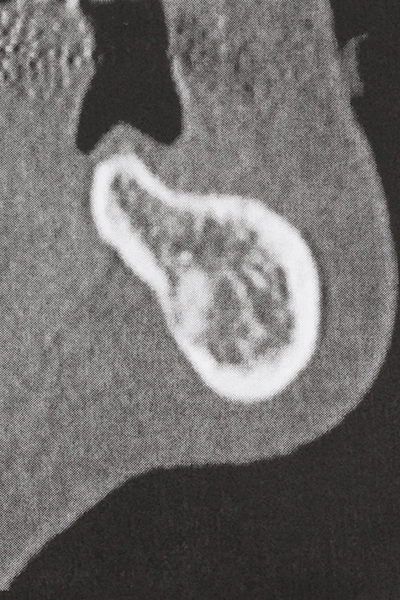

Piezosurgery has additional advantages when harvesting bone blocks. In addition to the high precision with osteotomy described above, the use of the thin saw tips specifically minimizes loss of material. Greater loss of material during harvesting can be expected with the thicker instrument tips, particularly when using Lindemann drills (Lakshmiganthan, Gokulanathan et al. 2012). The basal separation, which is necessary particularly for retromolar block transplants, is simplified by specially designed rectangular saws, with the result that piezosurgery is viewed as a precise, simple and safe procedure for harvesting retromolar bone blocks (Happe 2007) (Fig. 1-12).